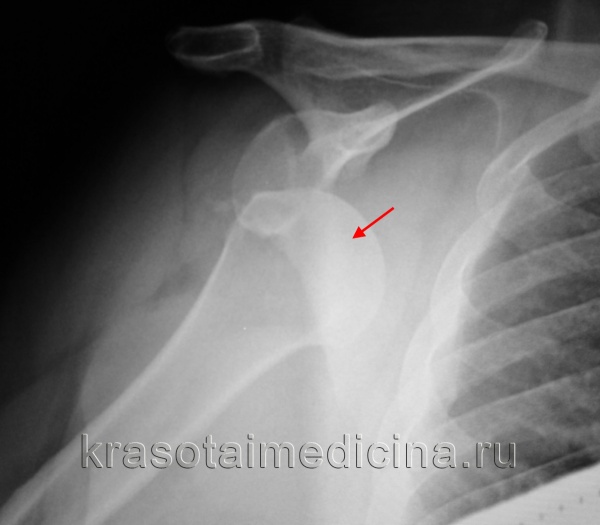

2. Рентгенография при переднем вывихе плеча:

• Передне-задняя проекция:

о Головка плечевой кости смещена медиально и вниз от суставной впадины

о Обычно вниз от клювовидного отростка

о Может быть блокирована передним краем суставной впадины при вколоченном переломе головки плечевой кости (повреждение Хилл--Сакса)

о Пожилые пациенты: перелом большого бугорка

(Слева) Передне-задняя рентгенограмма, пациент после вправленного вывиха: перелом Хилла-Сакса заднелатеральной части головки плечевой кости и небольшой перелом Банкарта.